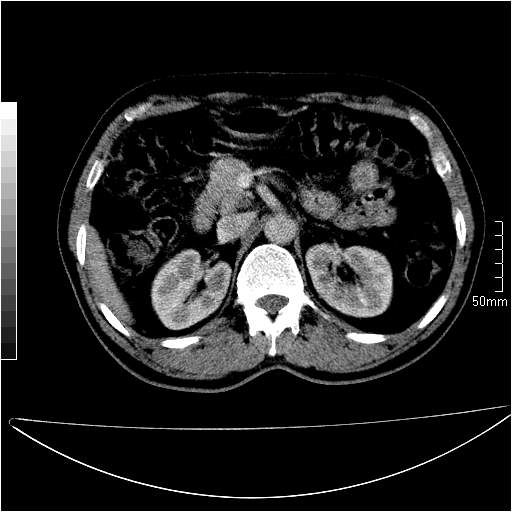

男性,54岁,皮肤黄染,搔痒一周余.b超示肝左叶回声异常.初步诊断1胆总管下段结石2胆囊结石伴慢性胆囊炎请各位战友帮忙看一下肝脏多发低密度如何解释恰当.增强效果不是很好.请大家见谅.

首先,胆总管下端结石梗阻伴肝内胆管扩张可确定。

另外,肝八段低密度占位,呈多灶性,考虑肝脓肿或肝癌可能,(图像质量欠佳)建议进一步检查。

由于胆囊窝内结构显示不清,肝脏病灶又邻近胆囊窝首先考虑胆囊癌肝受侵犯。而后因肝脏病灶强化有渐进改变,且相邻胆管扩张,故考虑肝胆管细胞癌待排。

左肝胆管细胞癌。

胆总管下端结石。